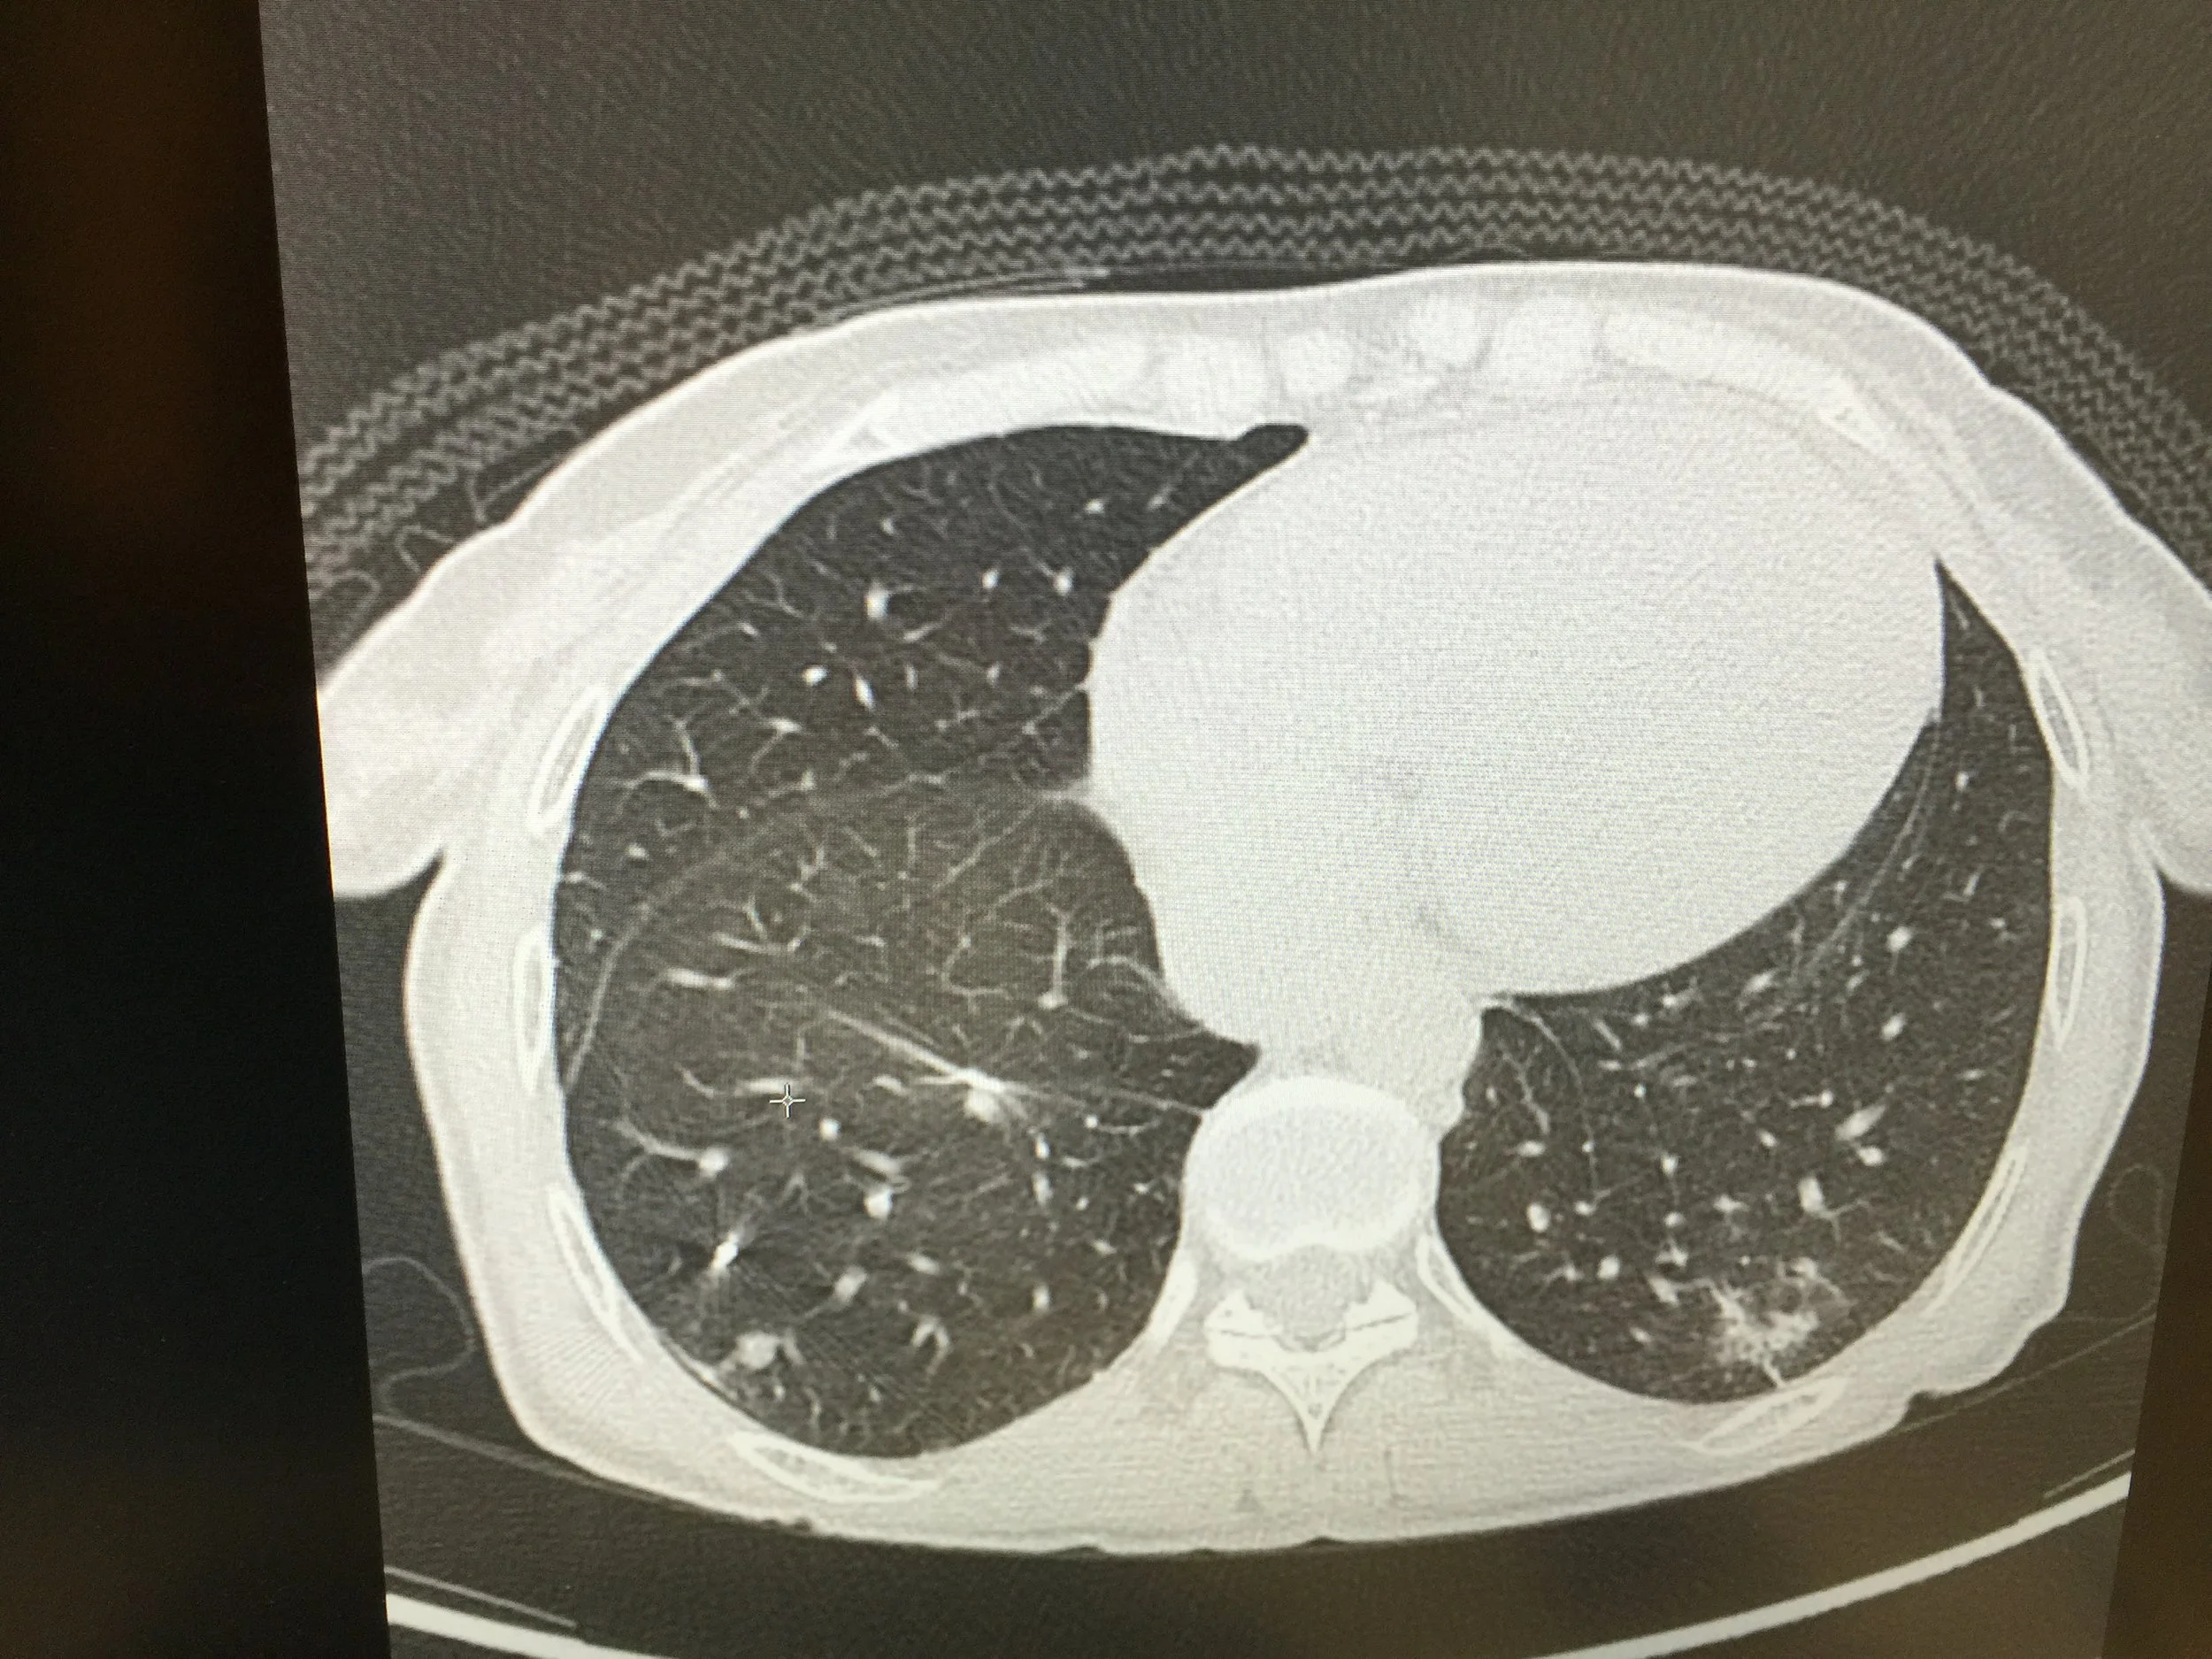

After my PET/CT scan in mid March 2018, I was told that after the four rounds of Cyberknife laser treatments, there were still three or four remaining ‘spots’ showing, all in my lower left lung lobe.  They were there in December 2017, but were very small then.  Three months later, it shows they have grown slightly.  What does this mean?  It’s impossible to say for sure without taking a biopsy and that means some form of cutting, so they will remain a mystery.  However, spots are spots, and given my current history, the most likely explanation is that there is some form of metabolic activity going on that is encouraging growth and expansion and this is not something I’m keen on.

Immediately following the March scan, I took a break from doctor’s visits and any further allopathic treatments.  These spots are still so small, it was decided that I would continue on with my ketogenic eating, exercise, intake of numerous anti-cancer supplements, newly added amino acids, meditation, yoga, healing sessions and recheck in three months.  This gives my body time to continue building immune strength and for me to experience some ‘BodyTherapy.’